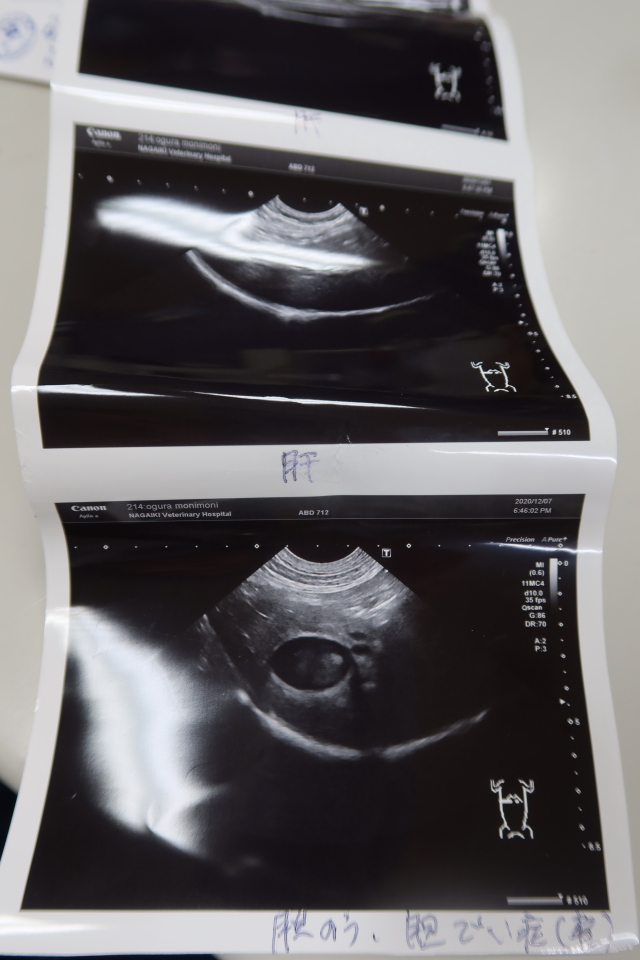

●(生まれて3回目の)エコー。

昨日も、3人で押さえつて、院長がエコーを操作しての計4人がかり。

【エコー診断の結果】

胆泥があるが(軽度の胆泥症)、先天的なものでわりとあることなので心配なし。

右腎、左腎、脾臓、膀胱、肝臓、副腎大丈夫。